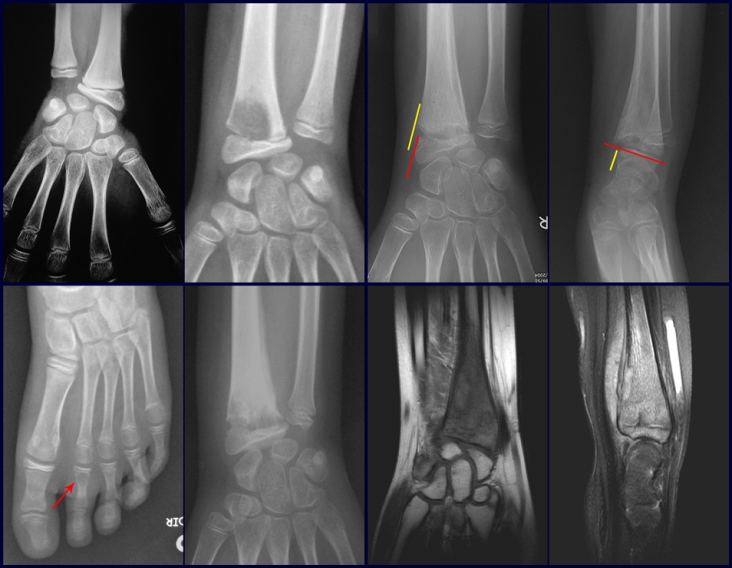

Exames de imagem: A imagem radiográfica é de rarefação óssea, arredondada ou ovalada, que se inicia na medular e progride com erosão da cortical óssea.

Na fase inicial as bordas são irregulares e mal delimitadas.

Na fase tardia pode ocorrer discreta esclerose ao redor da lesão. Nos ossos longos há reação periosteal evidente que se apresenta como múltiplas camadas lamelares grossas, que caracteriza as lesões benignas de evolução lenta ou a reação da osteomielite.

Este tipo de reação periosteal sólida diferencia o Granuloma Eosinófilo do Sarcoma de Ewing, onde a reação periosteal é lamelar fina, devido à rápida evolução do tumor maligno.

Outra diferença radiográfica entre essas duas lesões é que o tumor de Ewing precocemente apresenta tecido tumoral extra-cortical, de grande volume, o que não ocorre no Granuloma Eosinófilo.

Nos ossos chatos, como crânio ou pelve, a erosão acomete ambas as corticais de maneira irregular e assimétrica produzindo a impressão visual de um orifício dentro de outro orifício, denominada lesão em duplo contorno.